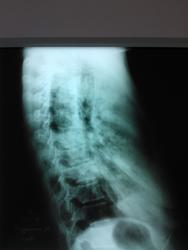

Анализы,конечно,дело интересное,но нам надо по рентгену что-то высказать.На ЛТГ-толстостенные полости,интересно,как фтизиатры от них отмахнулись.Пока затрудняюсь с ответом,ждём мнений заслуженных пользователей,например Nikolas.Интересен анамнез более ранний(перенесенные заболевания) и архив,если возможно.

Сложное дело, но во-первых, хорошо, что томограф работает.Жалко, что не удалось попасть в срединный срез, что с таким разбросом (6-10-13-16 см) не мудрено. Срез расчитывается по боковой томограмме от перекрестья задних отделов ребер до зоны интереса (в данном случае до уровня бифуркации), ну и плюс/минус 1см.

Можно замахнуться и на боковую томограмму, которая расчитывается по прямому снимку от остистых отростков до уровня корня легкого (как правило 5-6см), соответственно также и на столе, а потом отмечается расстояние от деки стола.

фтизиатр по флюшке написал центральный рак, после обзорной мнение его - двухсторонняя пневмония. мокроту еще не успела сдать, только сегодня назначили анализ мокроты. архива нет т.к. раннее не обследовалась. в отделение второй день. в боковой проекции томка не вышла, аппарат не смог снять, на кт попробуем уговорить родственников, сама не поедет.

А где же центральный рак на боковом снимке? Все те же инфильтраты, опухолевой массы не видно.. Тем более по-моему начинается обсеменение нижних отделов левого легкого.. Неужели больше нет сторонников тбц. Если на КТ не доедет, то пусть хоть мокроту как следует соберут посмотрят

На боковом снимке - "каша"

Для доказательства более целесообразна боковая томограмма